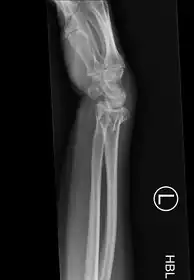

-

Bilateral Colles fractures/frontal -

Bilateral Colles fractures/lateral -

Colles fracture